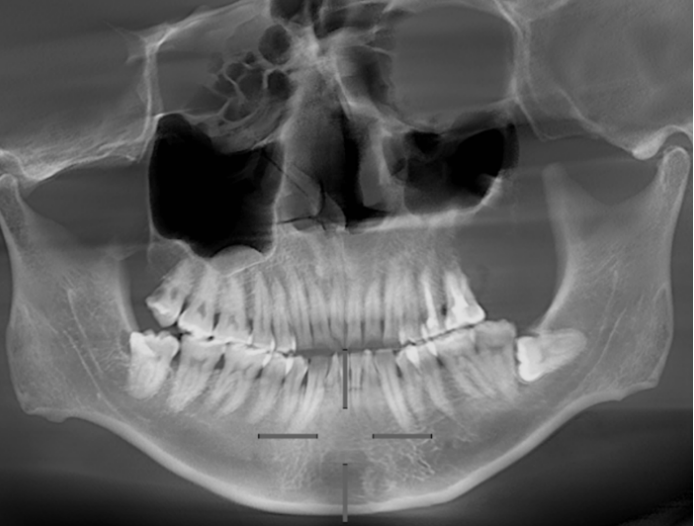

水母网12月18日讯(通讯员 王茜玮 李姝慧)五年前,曲先生因颌骨肿物在当地进行了手术切除,病理诊断为成釉细胞瘤。两年前复查时,发现原手术区再次出现异常阴影,开窗手术后确诊复发。如今,曲先生的病情达到需要再次干预的程度,于是他带着一份“厚重”的手术史,专程来到烟台市口腔医院寻求进一步治疗。

入院后,医生团队为曲先生进行了全面的检查与评估。鉴于成釉细胞瘤具有局部侵袭性和较高复发风险的特点,医疗团队制定了针对性的手术方案,为其进行了肿物切除手术。术后,曲先生恢复情况良好,目前正在康复随访中。

成釉细胞瘤是一种主要发生于颌骨的牙源性肿瘤,虽然被归类为良性,但其生长具有局部侵袭性,且术后复发率较高。该病多发于青壮年,初期往往没有明显症状,随着肿瘤缓慢生长,可能出现颌骨膨大、面部不对称、牙齿松动移位等情况。若肿瘤压迫神经,还可能引起下唇或面颊麻木;若体积过大,甚至可能影响吞咽、咀嚼功能。

成釉细胞瘤约占所有牙源性肿瘤的60%以上,其复发主要与肿瘤本身的侵袭性生长方式有关。目前常用的手术方式主要有三种: